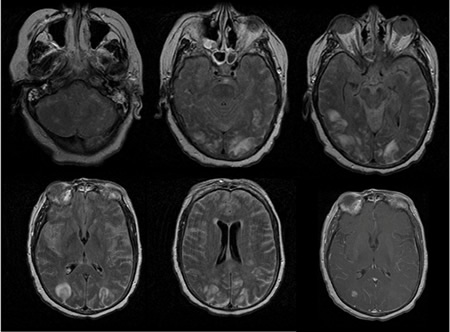

RNM cranioencefálica: o sinal pulvinar (um termo que se refere à hiperintensidade pulvinar bilateral) em um paciente com doença de Creutzfeldt-Jakob em imagens ponderadas por difusão

Do acervo pessoal de Leo H. Wang; usado com permissão